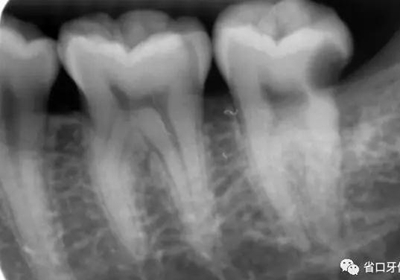

臨床檢查:37遠中鄰面探及深齲洞,探痛明顯,叩-,無松動,冷刺激痛明顯,去除刺激后疼痛延遲。X片示37遠中鄰面牙體低密度影累及髓角。

圖1 術前口內(nèi)照,37合面窩溝形態(tài)完好,

遠中牙體輕度“墨浸樣”變色,探及遠中齦下深齲洞

圖2 術前X片示遠中鄰面牙體低密度影累及髓角